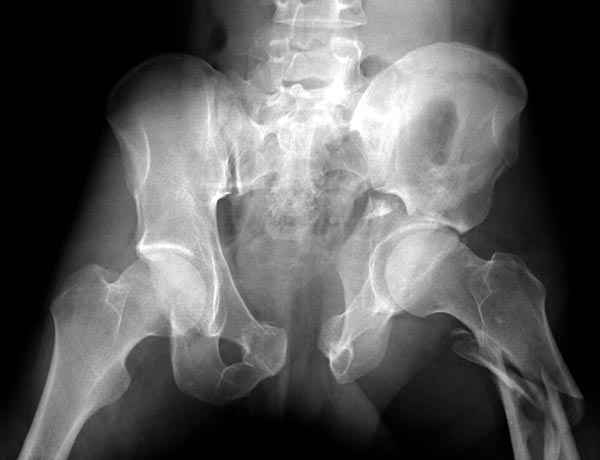

Из того минимума, что представлено, мне кажется, мы имеем дело с двухколонным переломом вертлужной впадины. Обычно медиальный (центральный) "вывих" головки встречаются в сложных двухколонных переломах со смещением.

Здесь несколько вариантов двухколонных свежих переломов, которые были оперированы из одного-заднего, а также из двух: переднего и заднего доступов.